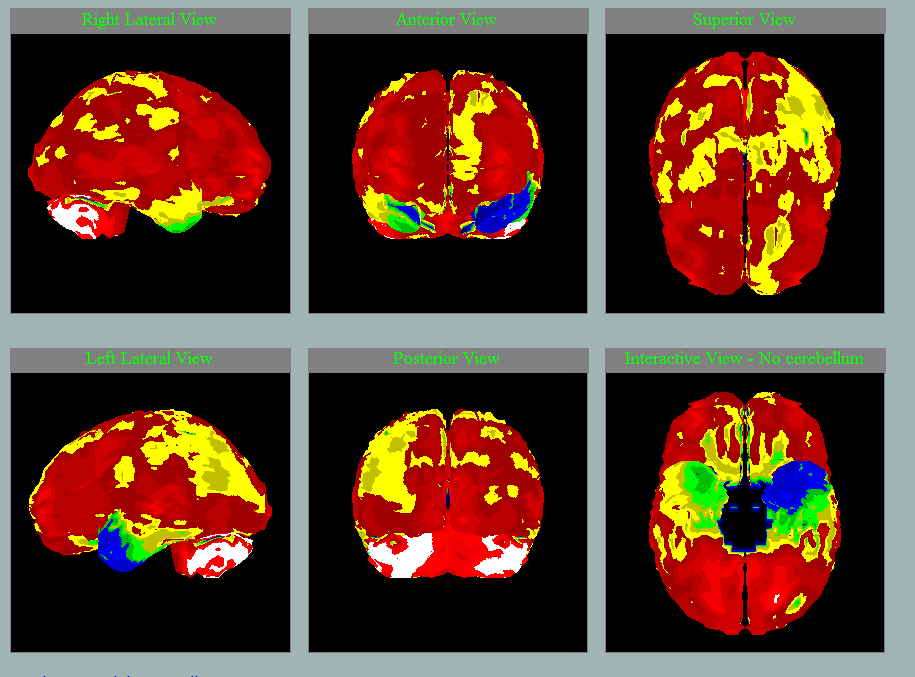

SPECT mozku u pacientky a její dcery

dcera, 54 let, VŠ

matka, 82 let

Hledejte ne 5 rozdílů, ale v čem se oba mozky podobají….